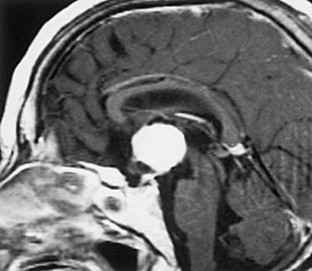

A chordoid glioma in the third ventricle was studied immunohistochemically and ultrastructurally. In this report, special attention is paid to the histogenesis in relation to the pathological appearance and unique anatomic location of this tumor. Light microscopic and immunohistochemical findings were similar to those reported previously. Ultrastructurally, microvilli were frequently seen, but three types of abnormal cilia were rarely observed. Basement membrane around the tumor cells and microvessels was extensive. Poorly to moderately developed intermediate (adherent) junctions were frequently seen. Resemblance of these ultrastructural features of the tumor to embryonic tanycytes suggests the tanycytic differentiation of chordoid glioma. Neuroradiologically, all of the previously reported cases of chordoid gliomas seem to arise in the anterior part of the third ventricular floor. This region includes the lamina terminalis, infundibular recess and median eminence, which corresponds to a tanycyte-rich area. These findings suggest a tanycytic origin of chordoid glioma.

Fig. 2.